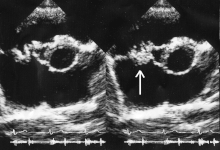

Vegetation on the tricuspid valve by echocardiography. Arrow denotes the vegetation.

In general, the Duke criteria should be fulfilled in order to establish the diagnosis of endocarditis.[12][45] Although the Duke criteria are widely used, they have significant limitations.[12] For example, the sensitivity of the Duke criteria for detecting infective endocarditis decreases when prosthetic heart valves are present.[12]